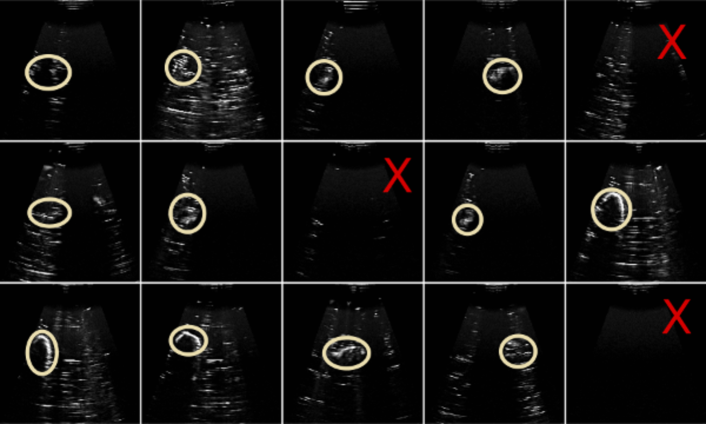

Figure 1 shows predicted reward sequences for sample expert demonstration traces held out from model training. It is clear that the ranking reward model captures the general improvements in image quality that occur as the demonstrator searches for a good scanning view, and that some searching is required before a good viewpoint is found. Importantly, the slack in the pairwise ranking model, combined with the model assumption that similar images result in similar rewards, allows for these peaks and dips in reward to be modelled, as probabilistic temporal ranking does not assume monotonically increasing rewards.

We qualitatively assessed the image regions and features identified using the reward model using saliency maps (Figure 1d), which indicated that the proposed approach has learned to associate the target object with reward.

Trials were repeated 15 times for each approach, alternating between each, and ultrasound gel was replaced after 10 trials. Each trial ran for approximately 5 minutes, and was stopped when the robot pose had converged to a stable point, or after 350 frames had been observed. A high quality ultrasound scan is one in which the contours of the target object stand out as high intensity, where the object is centrally located in a scan, and imaged clearly enough to give some idea of the target object size (see Figure 2).

As shown in Figure 11, the probabilistic temporal ranking model consistently finds the target object in the phantom, and also finds better rated images. Mean and standard deviations in image ratings were obtained using the rating model (see above) trained for reward evaluation using human image preference comparisons. The maximum entropy approach fails more frequently than the ranking approach, and when detection is successful, tends to find off-centre viewpoints, and only images small portions of the target object.